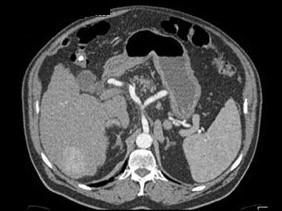

问题 男,44岁,患乙肝多年,现腹痛,腹胀,AFP增高,消瘦、乏力,影像检查如图,最可能诊断是 ( )

选项 A、肝硬化、肝癌 B、肝结节性增生 C、肝腺瘤 D、肝转移瘤 E、肝血管瘤

答案 A